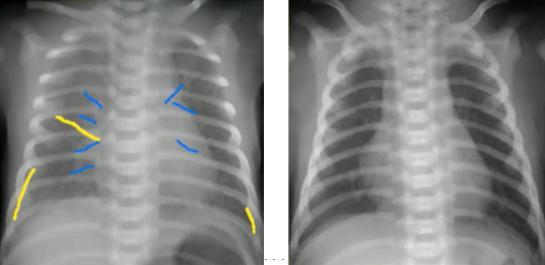

图9.肺实变(左)与肺不张(右)②细菌性与病毒性感染的鉴别

细菌性感染(支气管性肺炎):表现为沿着支气管分布的阴影;弥漫性毛绒状、边界不清,可延续到肺边缘;可伴有胸膜积液、空洞。

病毒性感染(间质性肺炎):表现为沿肺门分布的间质阴影;肺叶过度充气,表现为横膈膜变平;支气管增厚;可伴有分泌物阻塞导致局部不张。

图10.支气管性肺炎(左)与间质性肺炎(右)以下是细菌性感染的一些典型胸片: